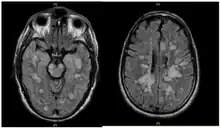

Fulminating ADEM showing many lesions. The patient survived, but remained in a persistent vegetative state

ADEM produces multiple inflammatory lesions in the brain and spinal cord, particularly in the white matter. Usually these are found in the subcortical and central white matter and cortical gray-white junction of both cerebral hemispheres, cerebellum, brainstem, and spinal cord,[16] but periventricular white matter and gray matter of the cortex, thalami and basal ganglia may also be involved.